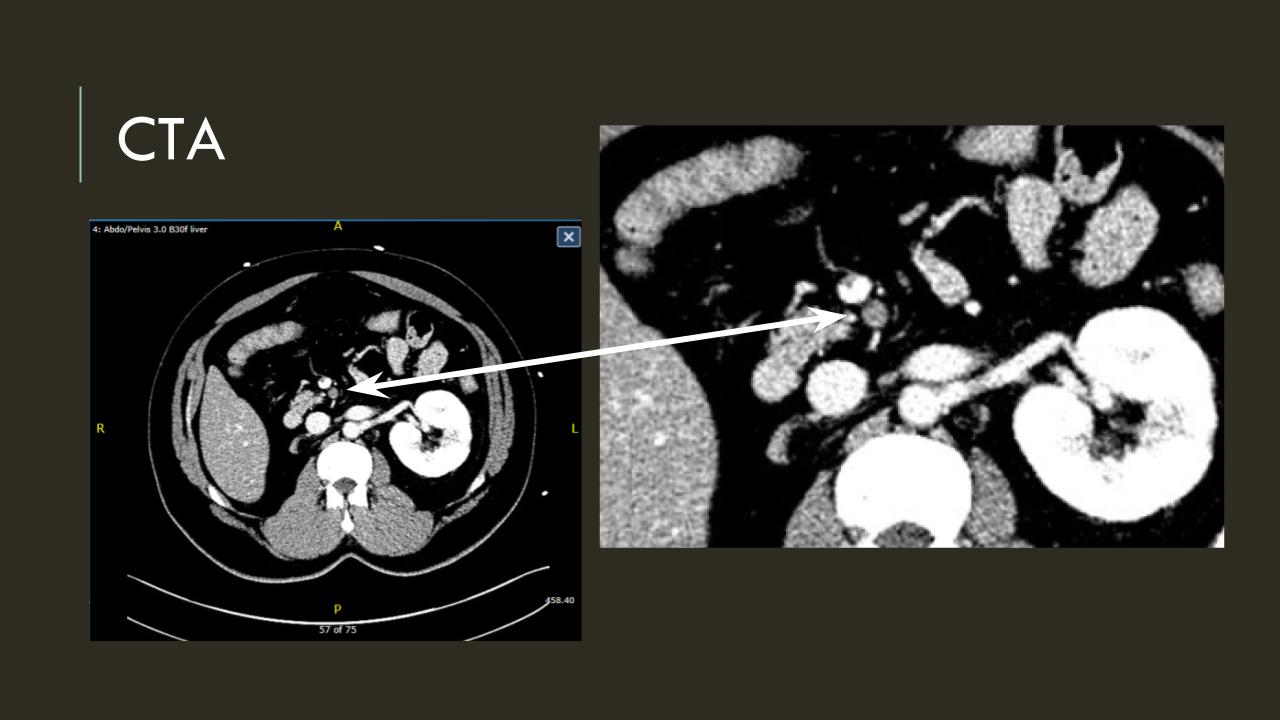

The EVAR was performed percutaneously. No endoleak was detected by completion arteriography (figure). He was soon discharged and was grateful. In followup, CT scan showed excellent coverage of the proximal and distal zones and absence of type III endoleaks. There was increased density to suggest a type II leak, but his inferior mesenteric artery was not the source of it. over a three year period, his aneurysm sac continued its 2-3mm of annual growth despite the presence of the the stent graft.

While CT failed to locate this endoleak, abdominal duplex ultrasound did showing flow from a small surface vessel (duplex below, figure at beginning of post). It was not the inferior mesenteric artery which can be treated endovascularly (link) or laparoscopically (link). CT scan suggested that it was one of those anterior branch vessels that one would encounter in exposing the aorta. Usually these were higher up as accessory phrenic arteries, but these fragile vessels, larger than vasovasorum, but smaller than named aortic branches, are seen feeding the tissues of the retroperitoneum.